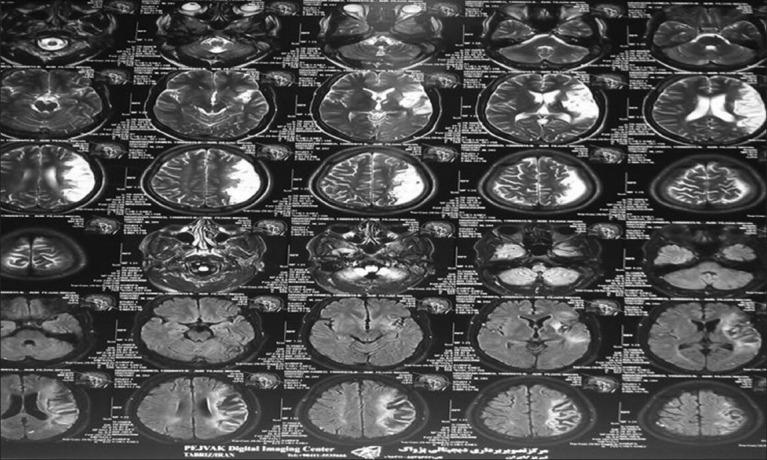

Myxomas, the most common primary cardiac tumors, are known as a source of cardiogenic emboli. The possibility of their early detection has made them of great importance for emergency medicines. Detection of the disease is probable at early stages using echocardiography and associate complications such as syncope, cerebral embolic ischemic strokes, and sudden death. We report experience of a rare case of juvenile acute stroke in a patient with cardiac myxoma affecting all cardiac chambers presenting to the emergency department. In young stroke patients with signs and symptoms compatible with cardiovascular involvement, cardiogenic emboli should be taken into consideration; early echocardiographic studies are highly recommended. Prompt myxoma resection is required in both asymptomatic and stroke patients in whom intravenous thrombolysis course has not been implemented due to any limitations.

黏液瘤是最常见的原发性心脏肿瘤,被认为是心源性栓子的来源。早期检测黏液瘤的可能性使其在急诊医学中具有重要意义。使用超声心动图在疾病早期阶段有可能检测到该病,并发现诸如晕厥、脑栓塞性缺血性中风和猝死等相关并发症。我们报告了一例罕见的青少年急性中风病例,该患者患有累及所有心腔的心脏黏液瘤,就诊于急诊科。对于有与心血管受累相符的体征和症状的年轻中风患者,应考虑心源性栓子;强烈建议早期进行超声心动图检查。对于因任何限制而未实施静脉溶栓治疗的无症状和中风患者,均需要及时切除黏液瘤。